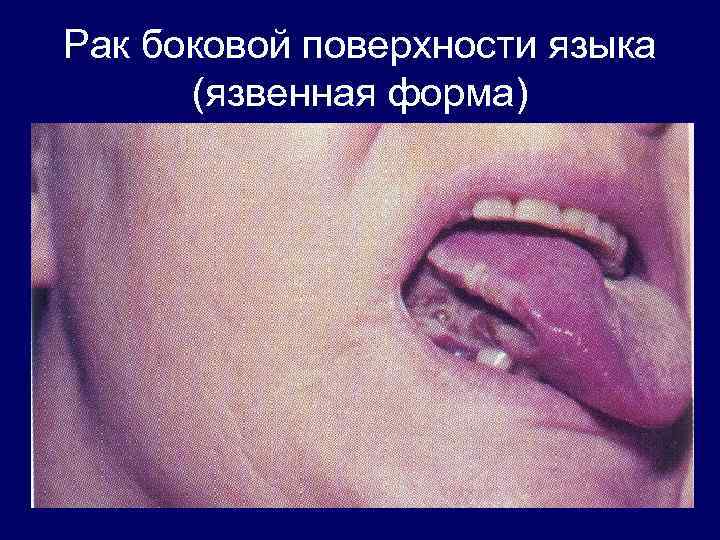

Рак боковой поверхности языка (язвенная форма)

Рак боковой поверхности языка (язвенная форма)